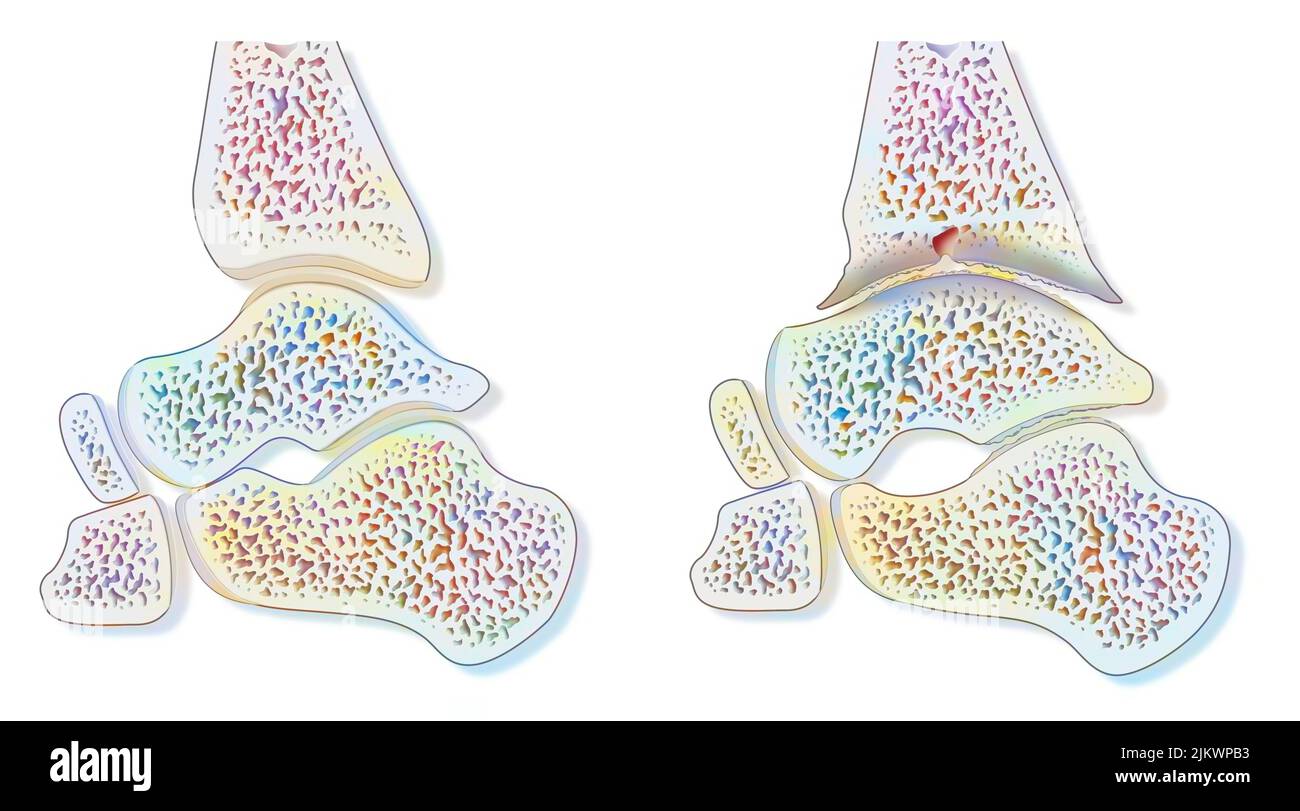

RF2K3D0JE–Illustration du rendu de l'hallux valgus ou du bunion x-ray 3D. Vue dorsale ou de dessus du pied gauche en bonne santé et blessé sur fond bleu. Anatomie, ostéol